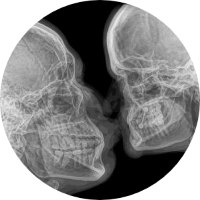

Humanos

• Niños

• Adultos

• Pacientes geriatras

• Seguimiento post cirugía ortopédica

HumanosRadiología Digital Directa

Posteriormente la radiología computarizada evolucionó a la radiología digital directa en donde podíamos hacer placas radiográficas y ver las imágenes en aproximadamente 18-20 segundos después de tomar la radiografía, y esto fue un gran avance para la comunidad de médicos, veterinarios, antropólogos, restauradores, paleontólogos, investigadores, y gente que requería radiografías y que por la logística que se requería y lo que implicaba no utilizaba esta herramienta de diagnóstico. En la actualidad, en la era de la inmediateidad podemos tomar placas radiográficas de alta definición en 2-3 segundos, en lugares remotos, sin necesidad de energia electrica ya que los generadores de rayos X funcionan con baterías, así como los equipos de radiología digital directa, esto ha permitido que el servicio de radiología se pueda proporcionar en cualquier lugar donde se requiera, pudiendo llevarse a donde están los pacientes u objetos a radiografiar, con las ventajas que esto implica. Los equipos actuales son ligeros, portátiles, de alta frecuencia, de alta definición, se ha optimizado la radiación que generan, lo que permite obtener imágenes radiográficas de muy buena calidad, con técnicas radiográficas inferiores a lo que se requería con radiología análoga. Hoy en día manejamos radiología digital directa de alta resolución.

Ideal para pacientes con incapacidad para trasladarse al hospital o moverse. Fracturados, con fijación externa, osteoporosis, niños, adultos, pacientes geriatras, seguimiento post cirugía ortopédica.

SI NO QUIERES IR AL HOSPITAL, AGENDA UNA CITA NOSOTROS VAMOS